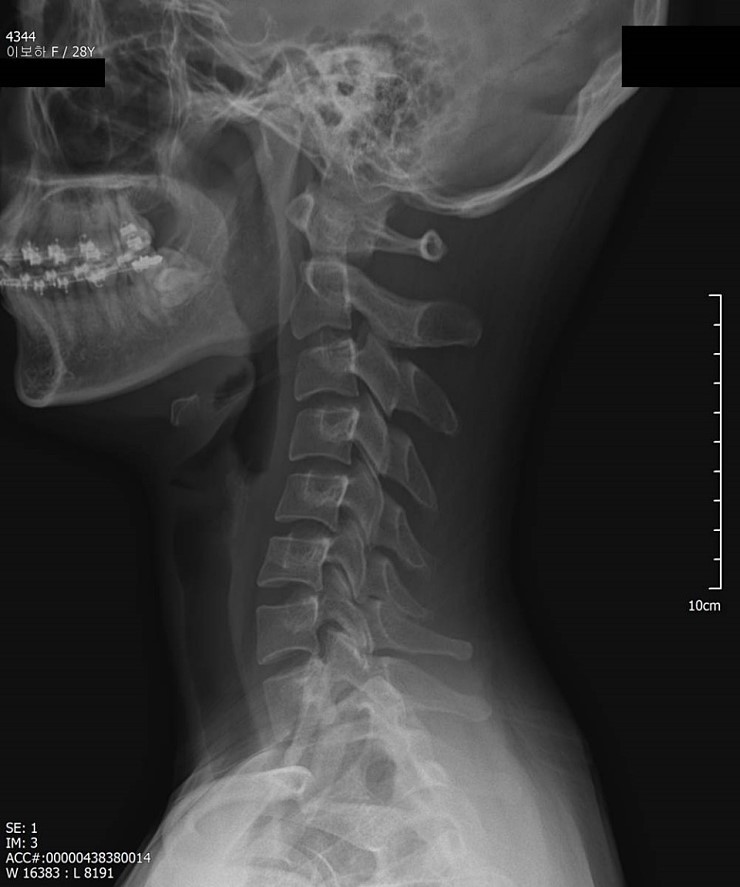

· 병명/수술여부 : 역C자목으로 인한 목,어깨통증 / 척추측만 / 요통(아래허리&우측골반) / 없음

[사진 - 경추 X-ray, 역 C자 (내 통증의 원인!!)] - 목이 매우 길기도 하고, 역 C자로 구조가 안좋음

(1) 척추의 정렬이 바로 잡히다 - 위 척추 X-Ray에서도 보이듯이 골반을 기준으로 일직선으로 선을 그었을 때 상체가 왼쪽으로 틀어져 쏠려있는 것을 볼 수 있습니다. 100일수련시작 전 사진에서도 몸이 왼쪽으로 많이 치우쳐있습니다. (사진이라서 왼쪽 오른쪽이 반대입니다~) 그리고 제 최대 컴플렉스.. 허리비대칭과 골반과 바로위쪽 툭 튀어나온 살 그러다 허리만 쏙 들어가는 이상한 몸매가 적나라하게 드러납니다. 그런데,, 어제 사진을 찍어보니 몸의 정렬이 정말 똑바라 졌습니다!!! 너무..놀라고..감격스러워서.. ㅠ_ㅠ 이맛에 SNPE 하나봅니다 정말

2) 무게중심중력선을 회복하다 - 목이 앞으로 나가있었는데 이제 딱히 힘을 안주고 신경을 크게 안써도 목이 자연스럽게 뒤로 이동했습니다. 전체적으로 무게중심중력선 회복이 많이 되었습니다